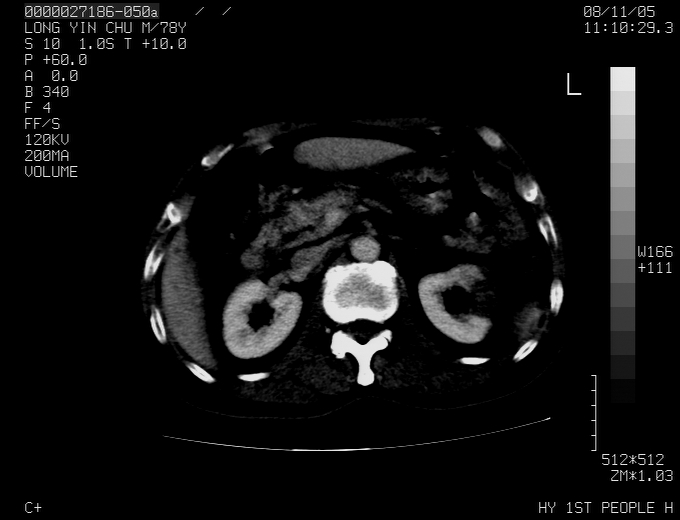

标题: CT16532:M78Y,肝脏病变,请会诊 [打印本页]

标题: CT16532:M78Y,肝脏病变,请会诊

腹胀,腹痛就诊,男性,78岁,外院b超未见异常。

肝ca,脾肾转移

支持脾肾转移瘤,双侧胸腔积液。

考虑弥漫性肝癌并脾及双肾转移.双侧胸水.

图片质量欠佳:多考虑:左侧肾癌。脾脏转移!胸膜转移!

肝脾肾转移瘤可能性大,左肾不除外梗塞,双侧胸水

考虑弥漫性肝癌并脾及双肾转移,双侧胸水。

考虑肝癌并双肾及脾脏转移;双侧胸腔积液。